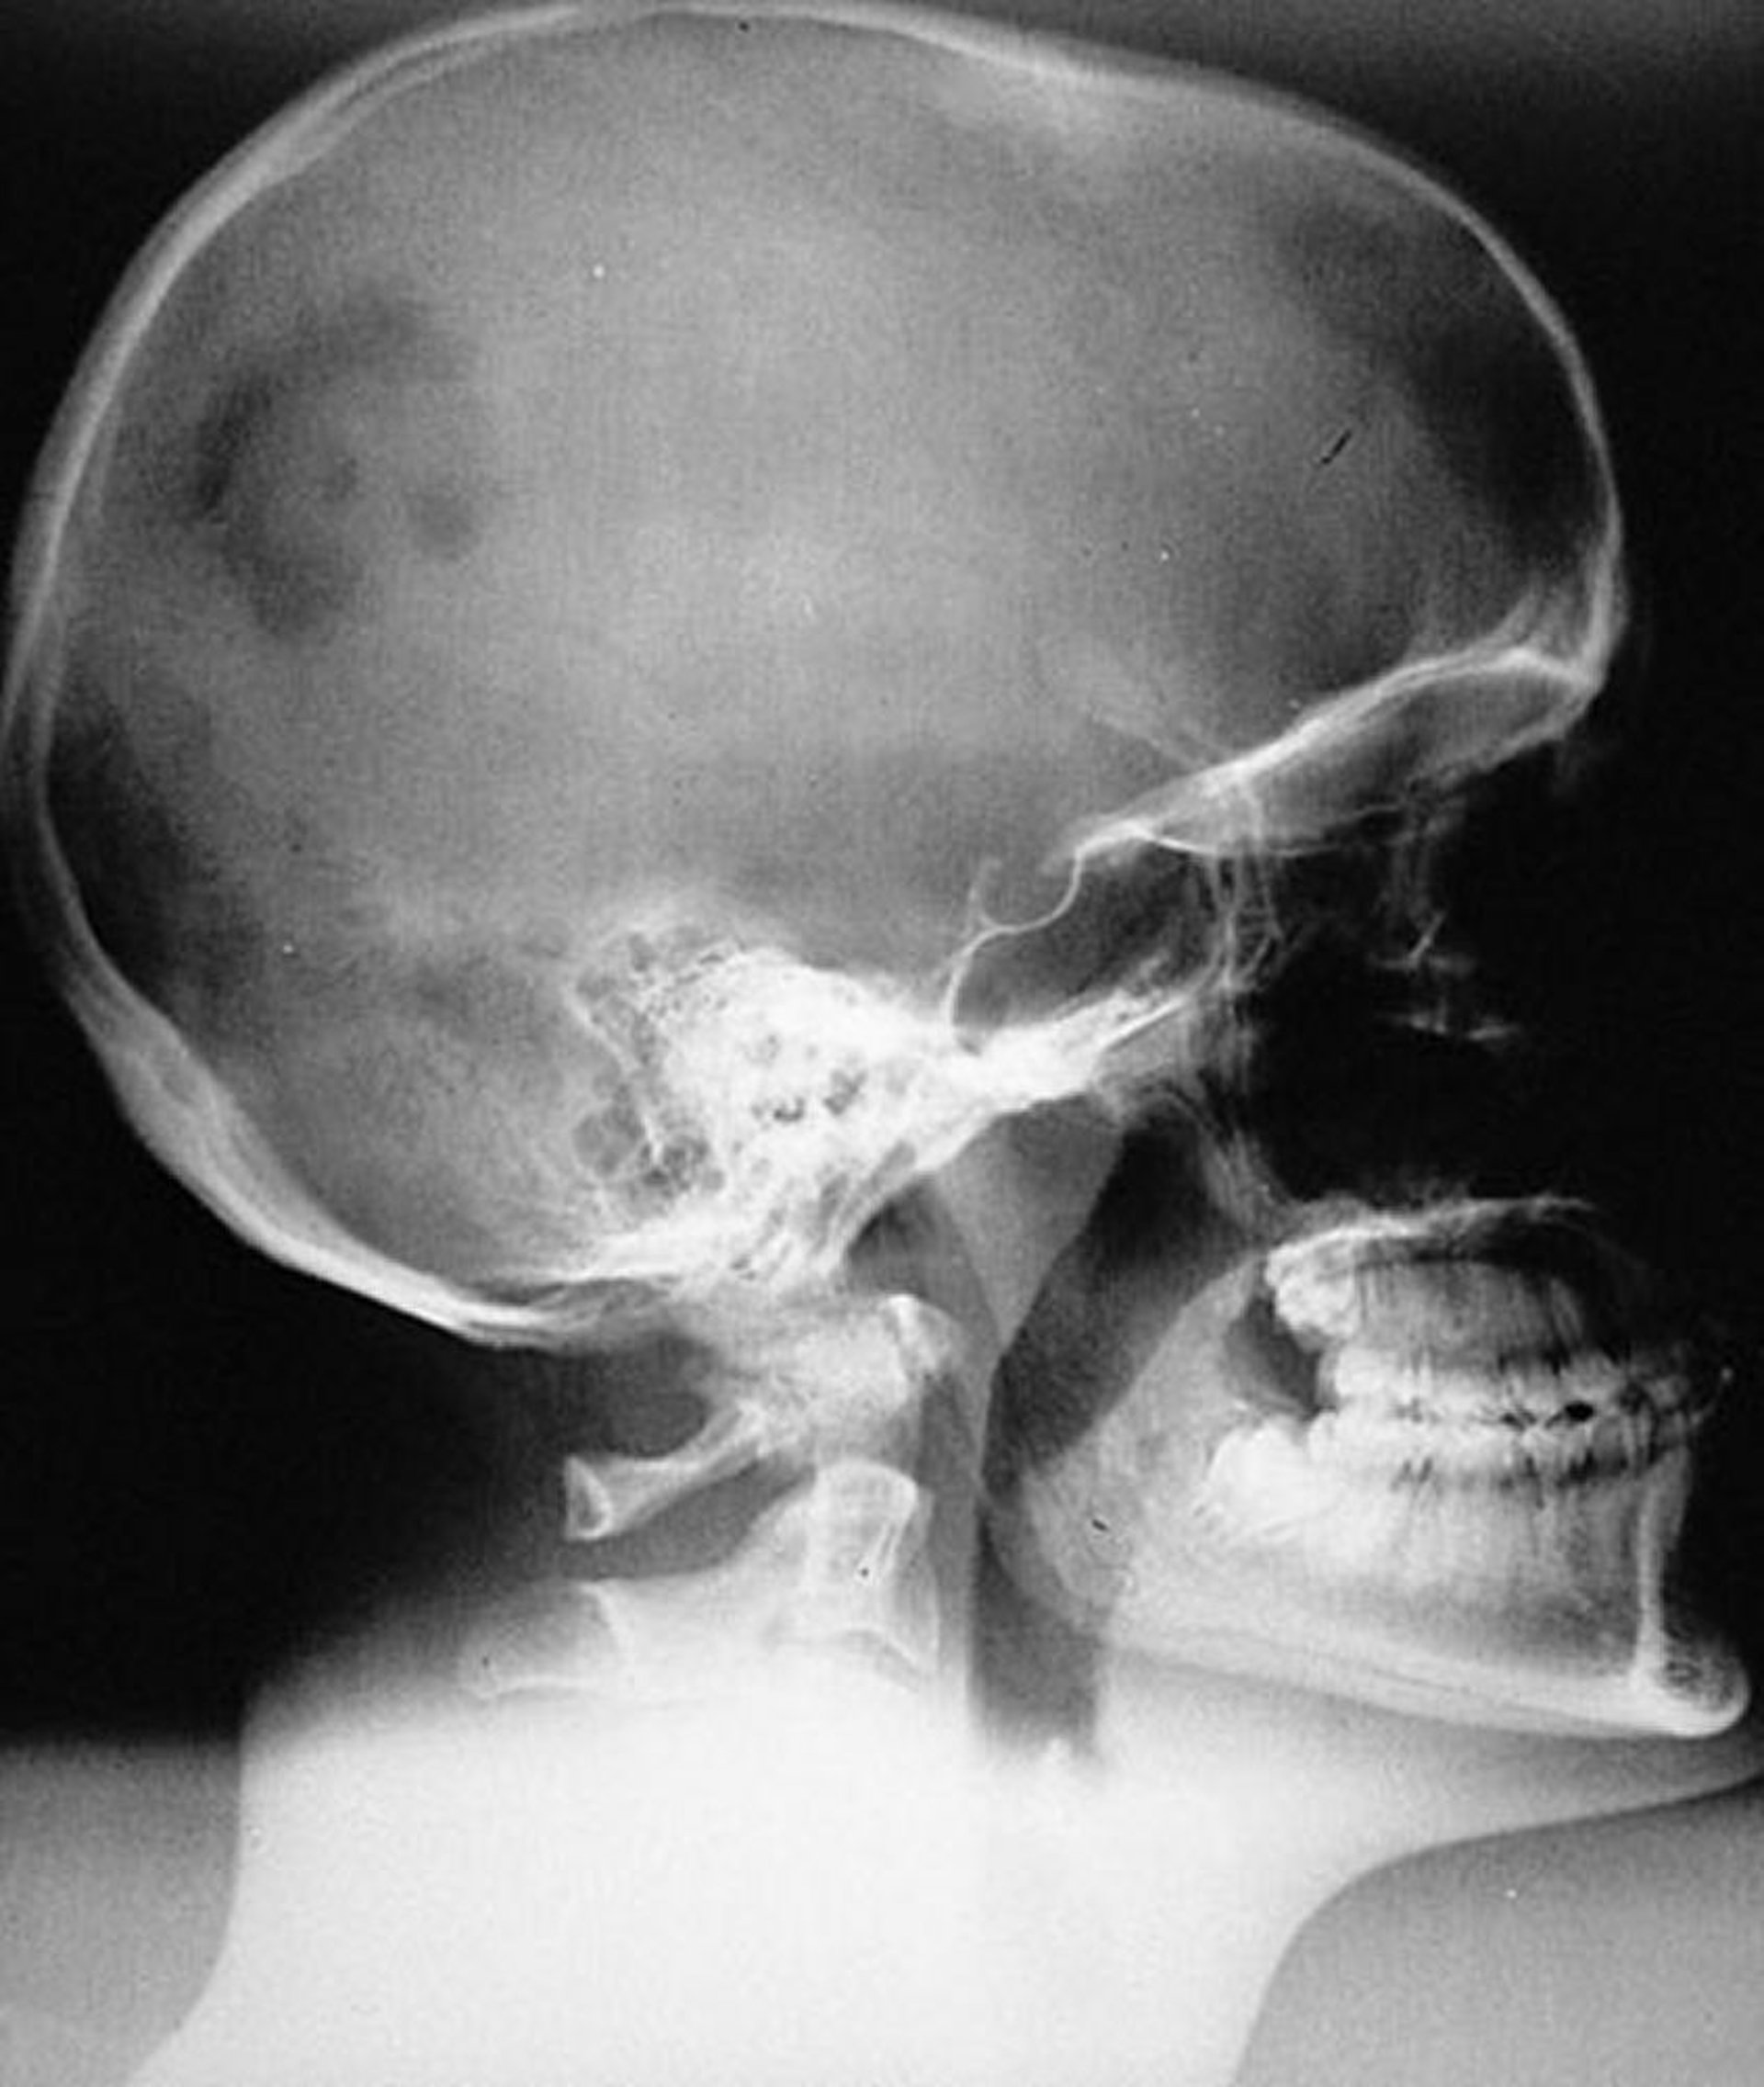

Histiocytose à cellules de Langerhans (Granulome éosinophile) du crâne

Aspect radiographique d'une lésion d’histiocytose à cellules de Langerhans monostotique unifocale typique (granulome éosinophile) du crâne. La lésion est nettement marginée mais non biseautée.

By permission of the publisher. From Swearingen B, Schaefer P, Primavera J, Klibanski A. In Atlas of Clinical Endocrinology: Neuroendocrinology and Pituitary Disease. Edited by S Korenman (series editor) and ME Molitch. Philadelphia, Current Medicine, 2000.